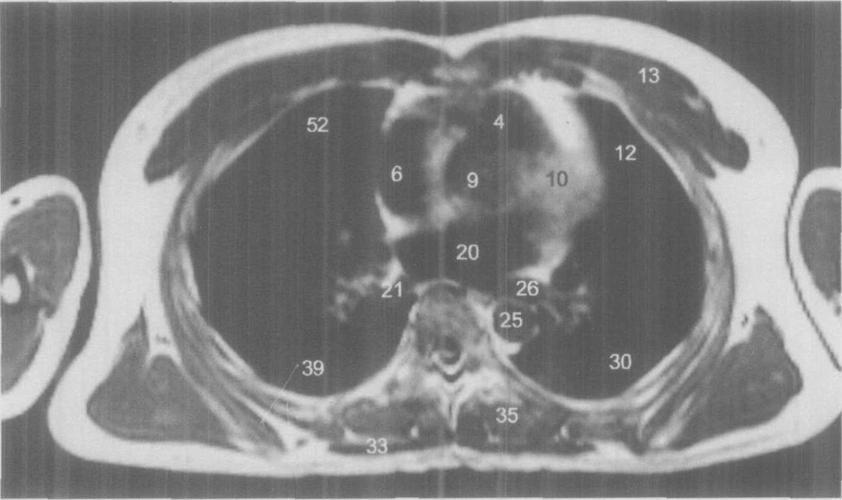

胸部ct解剖 肺动脉干与右肺动脉层面(平扫)

经右肺动脉横断层面

肺动脉干及左,右肺动脉层面ct和mri断层解剖